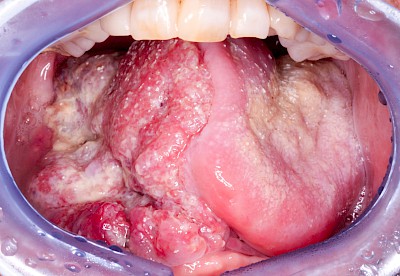

Einschmelzung & Geschwür

Das Risiko für Krebs der Mundhöhlen-Schleimhäute ist bei Menschen, die jahrelang übermäßig viel (Abusus) geraucht und erst recht lange übermäßig viel Alkohol getrunken haben, stark erhöht. Die Schleimhäute sehen dann aus wie "wildes Fleisch" – entweder mit blumenkohlartigen Auftreibungen oder aber es zeigen sich großflächige ungleichmäßig geformte Defekte und Einschmelzungen. Man spricht dann auch von einem Geschwür (Ulcus).

Entsteht der Krebs eher in tieferliegenden Schichten (z. B. im Bereich der Speicheldrüsen), sind die Auffälligkeiten nicht so deutlich. Hier fallen eher Seitenunterschiede links und rechts im Bereich der Mundhöhle auf. Auch plötzlich auftretendes und wiederholtes Nasenbluten, Einschränkungen der Atmung durch die Nase können Anzeichen für einen Tumor im Bereich der Nasen- oder Kieferhöhle sein.

Selten können auch Fibrome oder Druckstellen bei Zahnprothesen, wenn diese nicht erkannt und behandelt werden, in "wildes Fleisch" übergehen und hin zu bösartigen Tumoren entarten.

Bei allen diesen Auffälligkeiten ist eine sofortige (zahn-)ärztliche Abklärung zu veranlassen.